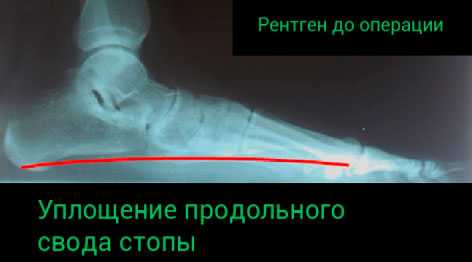

Ранняя диагностика не улучшается прямой рентгенограммой, тем не менее, обзор стопы покажет степень структурных изменений в 3-й стадии. Стандартная передне-задняя рентгенограмма показывает увеличение угла между продольной осью таранной кости и продольной осью пяточной кости, отведение переднего отдела стопы и смещение 2-й плюсневой кости. Длинная ось переднего отдела стопы больше не делит пополам угол заднего отдела стопы. В норме линейная связь между тараном, ладьей, медиальной клиновидной и первой плюсневой потеряна на боковой рентгенограмме. Если ситуация прогрессирует, то проявляется остеоартрит 1-го плюснефалангового сустава, вторичный по отношению к hallux limitus.

Рентгенографию. Этот метод обеспечивает нас изображениями плотных анатомических структур, например, костей. Он позволяет выявить в т.ч. дегенеративные изменения суставов. Если планируется оперативное лечение, то рентгенография позволяет выполнить необходимые измерения и выбрать наиболее оптимальную тактику оперативного лечения.

![плосокстопие тяжелой степени]()

![тяжелое плосокстопие]()